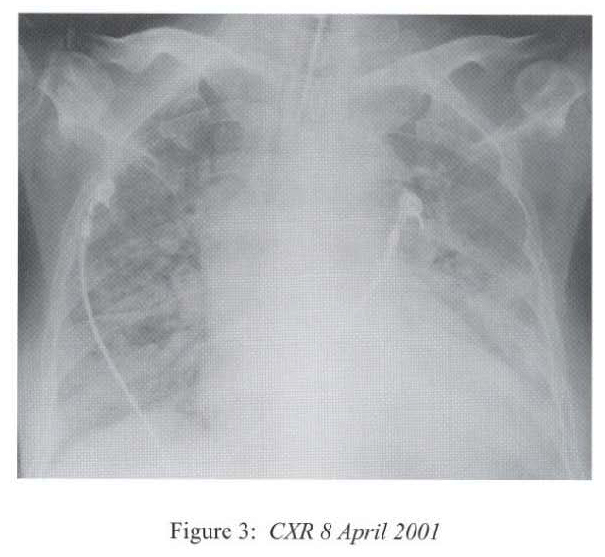

The respirology team was consulted at this time and we took over the case and managed her in the High Dependency Unit. The differential diagnoses included uncontrolled bacterial or fungal pneumonia, Pneumocystis carinii pneumonitis, viral pneumonitis, autoimmune pneumonitis, massive pulmonary embolism and massive pulmonary haemorrhage. She was treated with broad-spectrum antibiotics (piperacillin/tazobactam, amikacin) together with intravenous gancyclovir and cotrimoxazole. Supportive treatment included inotropes infusion, peritoneal dialysis, parenteral nutrition, and optimization of mechanical ventilation. Hydrocortisone was continued since she has been on systemic steroid for 3 months and the haemodynamic state was unstable. Bronchoscopy via the endotracheal tube showed copious mucoid secretions arising from both lung bases, and there was patchy mucosal excoriations involving the lower lobes. There was no sign of pulmonary haemorrhage. No transbronchial biopsy was attempted as she was on positive pressure ventilation and in critical state. CXR after bronchoscopy showed rapid resolution of pneumonia shadows in multiple areas (Figure 4).

Radiological features are also diverse and variable 15,16.On the chest radiograph, early signs include miliary shadows, diffuse reticular interstitial opacities, patchy alveolar opacities, segmental or lobar opacities. In the advanced stage, there can be extensive airspace shadows affecting both lungs, with occasional pleural or pericardial effusion. Without treatment, ARDS quickly evolves. Rarely, ARDS develops after antihelminthic treatment due to release of toxic breakdown products 17.On the abdominal radiograph, there can be thickened mucosal folds, segmental small bowel dilatation or perforation. Among all these variable radiological features, a characteristic pattern of Strongyloides hyperinfection has been described by the radiologists of Hong Kong, which consist of fleeting and rapidly changing CXR signs, predominant small bowel abnormality on AXR, and close temporal relationship of CXR & AXR signsl8. Detection of larvae in stool or other specimens is difficult (Table 1). Serological diagnosis19 is an attractive alternative but it is not available in Hong Kong.